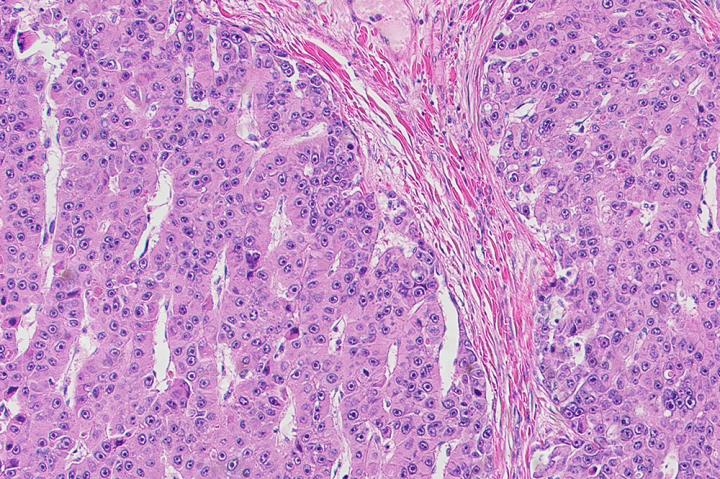

image: New drugs to eliminate fibrolamellar tumors cells, pictured here, were identified using an expedited approach.

Treatment options for a deadly liver cancer, fibrolamellar carcinoma, are severely lacking. Drugs that work on other liver cancers are not effective, and although progress has been made in identifying the specific genes involved in driving the growth of fibrolamellar tumors, these findings have yet to translate into any treatment. For now, surgery is the only option for those affected--mostly children and young adults with no prior liver conditions.